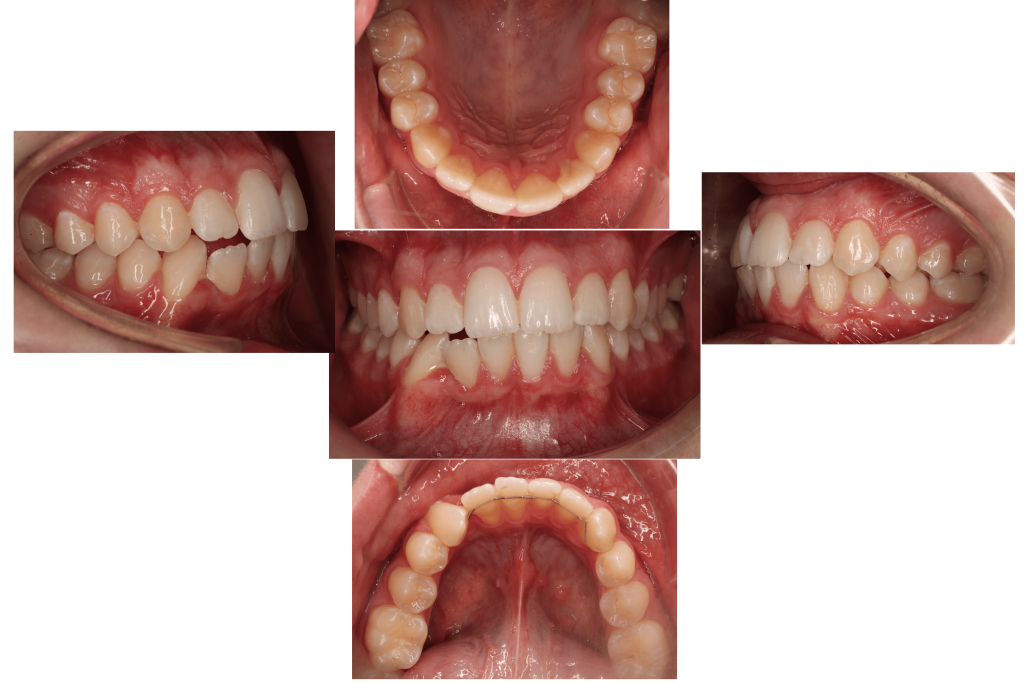

* 2 zgornja in spodnja retencijska žička

*2.Retencijske žičke so v uporabi od leta 1970. Fiksacija zob z retencijsko žičko, ki je nalepljena na notranji strani zob, se je izkazala za zelo priljubljeno, saj prepečeuje premike zob, kjer je recidiv zelo verjeten in snemni retencijski aparati niso zanesljivi, prav tako ni potrebno pacientovo sodelovanje. Po množični in dolgotrajni uporabi pa se je izkazalo, da te žičke niso tako nedolžne in lahko pride do stranskih neželjenih učinkov.

Leta 2022 je bila narejena prva študija o stranskih učinkih retencijske žičke. V ortodonstkih krogih je pojav dobil ime WIRE-SINDROM. Nov pojem wire sindrom se nanaša na premike zob, ki jih je mogoče opredeliti kot nenormalne, nepričakovane, nepojasnjene ali prekomerne premike zob, ki jih še vedno drži nepoškodovana ortodontska retenerska žica brez odstopitve ali zloma, kar vodi do razvijajočih se estetskih in/ali funkcionalnih posledic, tako zobnih kot parodontalnih.

Primer iz naše ambulante

Wire sindroma je nov pojav in je zaskrbljujoč za ortodonte, splošne zobzdravnike in parodontologe predvsem pa za paciente. Pomembno je, da primere odkrijemo zgodaj in se takoj učinkovito preprečijo nadaljni neželeni premiki zob in z njimi povezane posledice za dento-parodontalno tkivo ter se odločimo za ustrezno terapijo. Sporočilo akademske stroke pa je, da so potrebne dodatne klinične študije za razjasnitev etiopatogenih mehanizmov žičnih sindromov in njihovih kliničnih vplivov, kar bo akademski stroki na koncu omogočilo, da kliničnim ortodontom predlagajo učinkovite preventivne ukrepe.